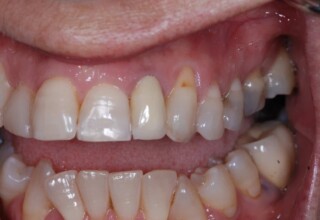

Οι όψεις ρητίνης προσφέρουν έναν οικονομικό τρόπο αισθητικής βελτίωσης της εμφάνισης των προσθίων δοντιών ενίοτε και των προγομφίων. Οι δυνατότητες τους πολλές, μπορούν να κάνουν και θαύματα! Ο μονός περιορισμός η κλινική ευχέρεια και η φαντασία του επεμβαίνοντος. Σε αυτήν την ασθενή οι τέσσερεις άνω τομείς είχαν ο καθένας το δικό του πρόβλημα(δυσχρωμία, απόκλιση) και επιπλέον: διαστήματα, πολλαπλές αποχρώσεις, κακή σχέση μεταξύ τους και με τα ούλα. Αποκαταστάθηκαν με τέσσερεις άμεσες όψεις ρητίνης (η μια πάνω σε στεφάνη πορσελάνης εμφυτεύματος!!!) οι οποίες κατασκευάστηκαν ενδοστοματικά!